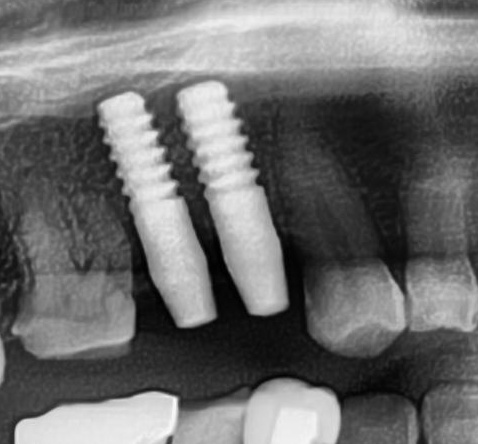

今回の患者様はインプラント植立を希望され、右上4番目・5番目の2本の植立が決まりました。

開けた穴に、専用道具を使ってネジを締めるように長さ2センチ程のインプラントを骨に埋め込んでいきます。

しっかりとインプラント埋め込まれた後は、動揺がないか、噛んだ時に当たらないかなどを確認して、最後にパノラマ写真を撮影して今回のオペは終了となりました。